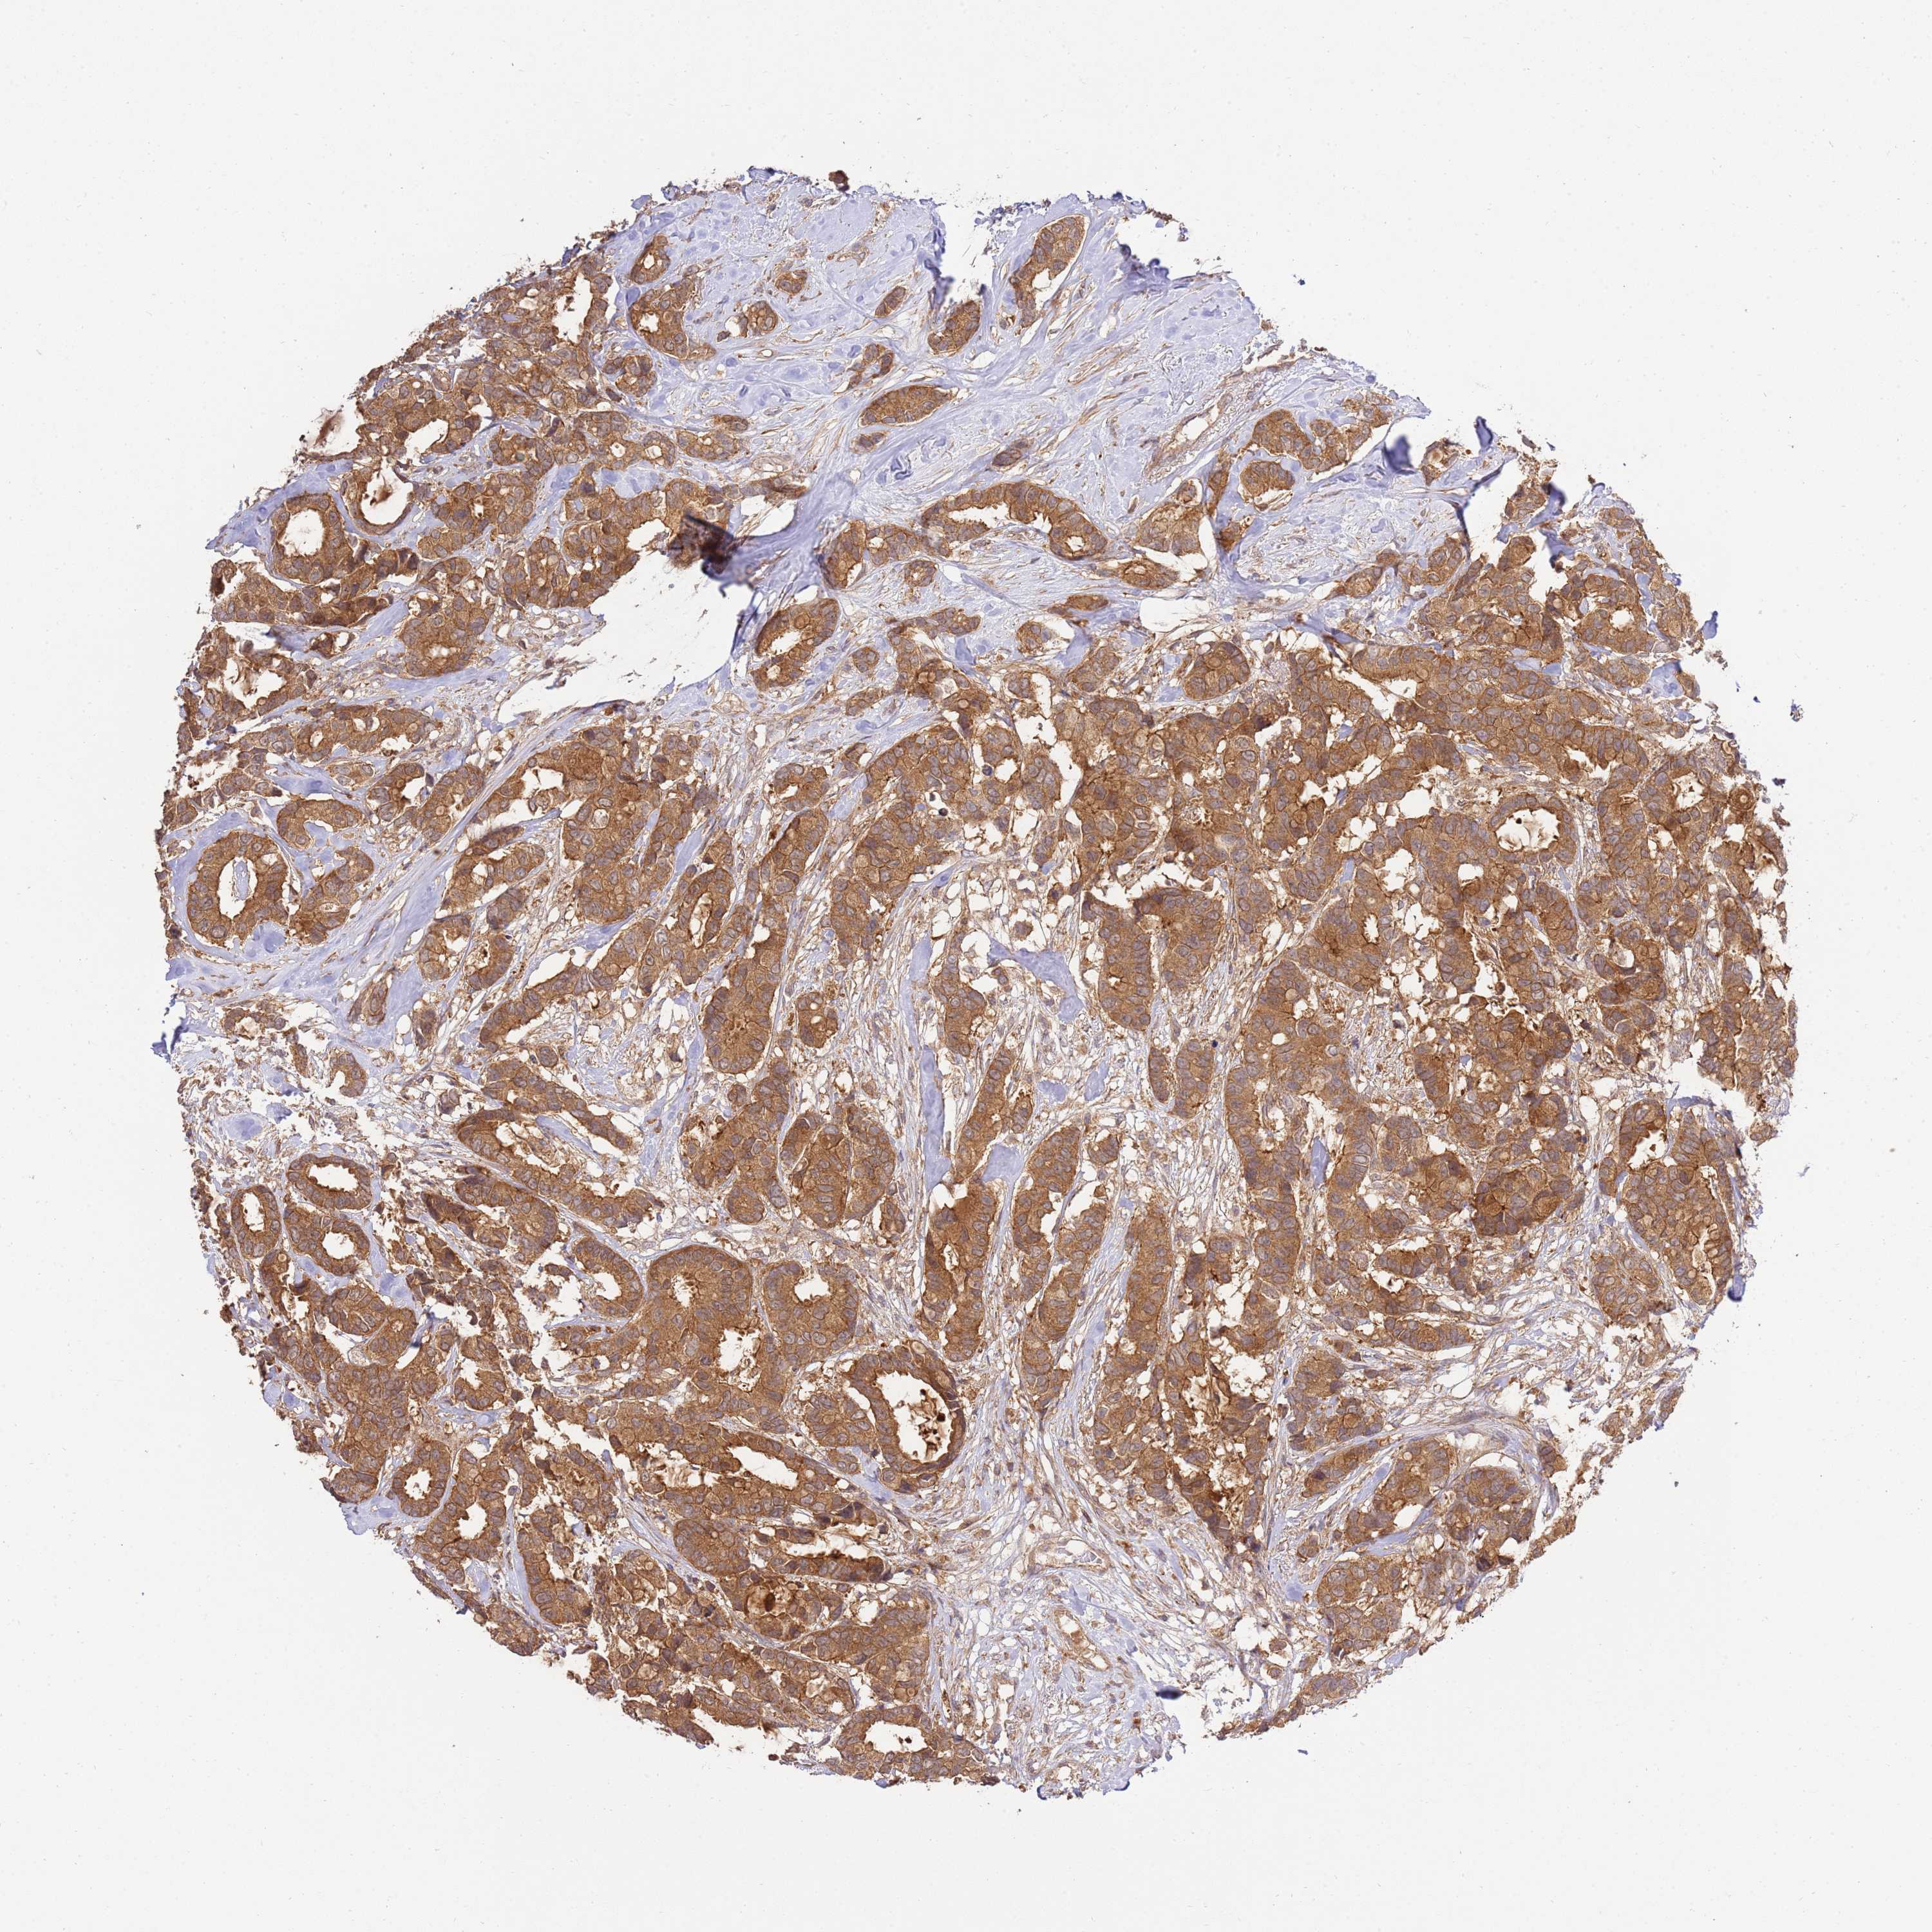

BRCA TCGA BRCA VALIDATION PROTEIN EXPRESSION

ANTIBODIES

AND

VALIDATION